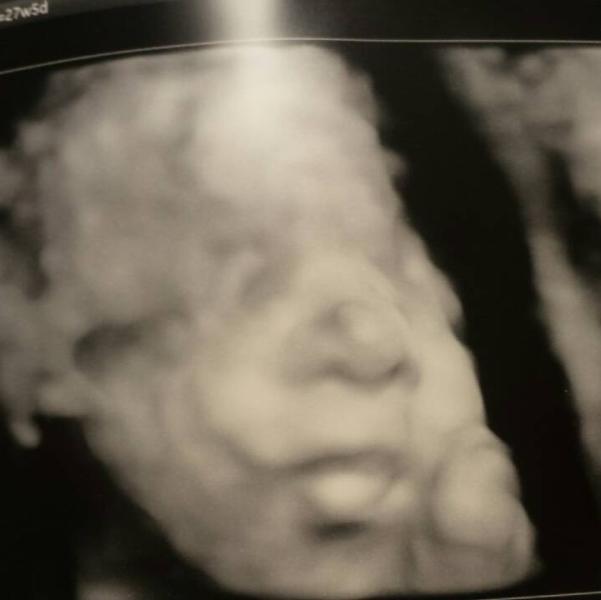

My beautiful baby girl!